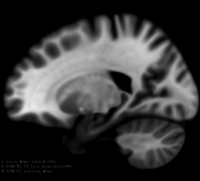

This module offers a simulation toolkit for baseline Multiple Sclerosis (MS) brain lesion volumes (given a lesion load) and longitudinal image simulations, respectively. In summary, a statistical lesion database is generated based on a set of manual lesion mark-ups, being non-linearly registered to MNI152 space (isotropic 1mm of voxel resolution). Using a small set of parameters (lesion load, lesion homogeneity, lesion intensity independence and lesion variability), it is possible to generate a broad range of MS lesions patterns in multimodal MRI imaging techniques (at moment, T1, T2, T2-FLAIR, PD, DTI-FA and DTI-ADC images are provided).